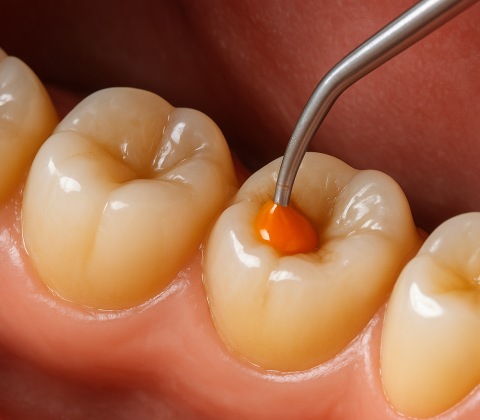

کفبندی در دندانپزشکی چیست و چه کاربردی دارد؟ بررسی کامل مراحل و مزایا

کفبندی در دندانپزشکی یکی از مراحل مهم در درمان پوسیدگیهای عمیق و آمادهسازی دندان برای ترمیم یا روکش است. این فرآیند به حفظ سلامت پالپ د